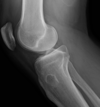

What are some investigations to do if you suspect osteomyelitis?

- Routine bloods (FBC, CRP, ESR) - Blood cultures - Plain film radiographs (see image) **- Definitive diagnosis is MRI** **- Gold standard is from culture from bone biopsy** at debridement